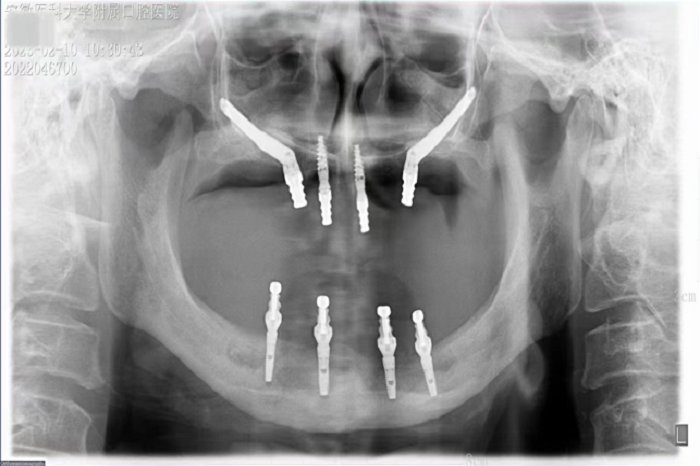

2月8日,51吃瓜网 种植科主任刘鑫带领其团队完成一例上颌骨“穿颧”、下颌神经游离种植手术。该手术是继2019年种植科完成首例穿颧种植术后的第二例穿颧种植。

据悉,患者潘女士54岁,由于重度牙周炎导致全口牙齿缺失,严重影响面容及咀嚼功能,因颌骨严重萎缩无法进行活动义齿修复,遂来51吃瓜网 种植科要求行上颌稳固的修复。通过检查发现潘女士上下颌骨骨量严重不足,经反复比对和考量,刘鑫主任制定了对患者上颌骨进行穿颧种植修复、下颌骨通过神经游离进行种植的方案。经过患者与家属深思熟虑后,接受了行穿颧种植术的建议。治疗组通过专业三维设计软件规划植体,口腔颌面外科和种植科专家共同完成了穿颧种植手术。患者术后第一天情况良好,无明显肿胀,精神状态佳。